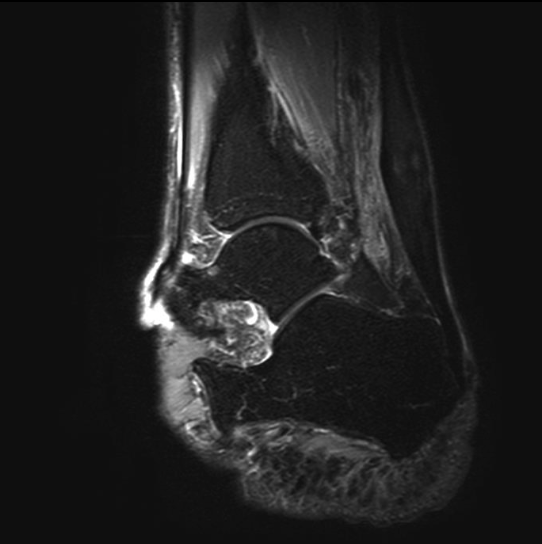

Ultrasound or MRI when needed to assess tendon degeneration

Insertional Achilles tendinopathy

Occurs where the tendon attaches to the heel bone

Often associated with bony irritation at the heel

Haglund’s deformity

A bony prominence at the back of the heel

Can worsen insertional Achilles pain